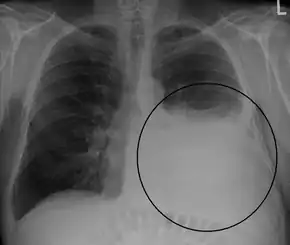

A pleural effusion appears as an area of whiteness on a standard posteroanterior chest X-ray.[9] Normally, the space between the visceral pleura and the parietal pleura cannot be seen. A pleural effusion infiltrates the space between these layers. Because the pleural effusion has a density similar to water, it can be seen on radiographs. Since the effusion has greater density than the rest of the lung, it gravitates towards the lower portions of the pleural cavity. The pleural effusion behaves according to basic fluid dynamics, conforming to the shape of pleural space, which is determined by the lung and chest wall. If the pleural space contains both air and fluid, then an air-fluid level that is horizontal will be present, instead of conforming to the lung space.[10] Chest radiographs in the lateral decubitus position (with the patient lying on the side of the pleural effusion) are more sensitive and can detect as little as 50 mL of fluid. At least 300 mL of fluid must be present before upright chest X-rays can detect a pleural effusion (e.g., blunted costophrenic angles).

Massive left-sided pleural effusion (whiteness) in a patient presenting with lung cancer.